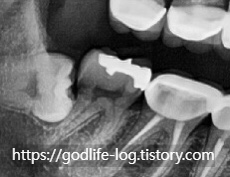

사랑니때문에 어금니에 충치가 생김

사랑니 발치 후 신경치료한모습

위 사진과 같이 주로 아래쪽에 있는 사랑니는 수평으로 매복되어 있는 경우가 많습니다. x-ray사진상으로는 치아가 잘 보이지만 실제 구강 내에서는 사랑니의 일부분만 보입니다. 맨 끝에 있는 어금니와 사랑니 사이에 음식물이 끼면 음식물이 잘 안 빠지고 그것 때문에 잇몸에 염증이 생기면서 잇몸이 붓고 피가 나고 정말 심한 경우에는 입을벌리기 힘든경우까지 생길 수 있습니다. 또 이런게 반복되면서 사랑니가 아닌 제2대구치라고 불리는 어금니에 영향을 주게됩니다. 위 사진과같이 충치가 심하게 생길수도있고 염증이 생기면서 사랑니와 어금니 사이에 있는 잇몸뼈를 소실되게 할수도 있습니다.이렇게 문제가 생기는 경우엔 사랑니를 발치가 필요합니다. 사랑니때문에 한번 염증이 생기면 계속 염증이 생기고, 앞치아에 안좋은 영향을 줄 수 있습니다.

위 사진은 충치가 있어서 사랑니 발치 후 신경치료를 하고 치아를 씌워서 살린 경우이지만 충치가 너무 심한경우에는 어금니까지 발치를 할 수도 있습니다.